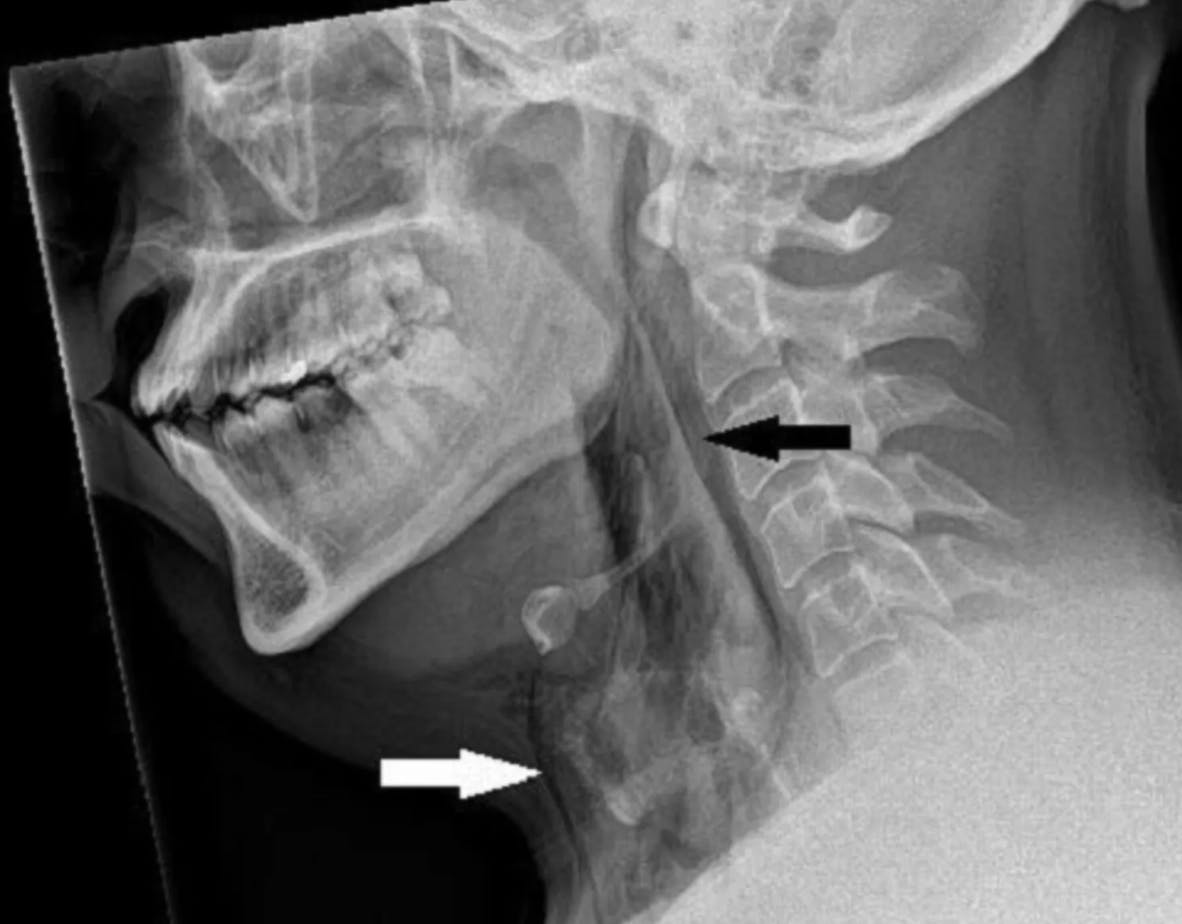

Manden, der har høfeber og altså ofte døjer med snue, blev både røntgenfotograferet og CT-scannet, og her fandt lægerne ud af, hvorfor manden havde så stærke symptomer fra halsregionen.

Ved at undertrykke sit nys blev trykket mod mandens øvre luftveje op mod 20 gange højere end normalt, og den store kraft havde revet hans luftrør i stykker.